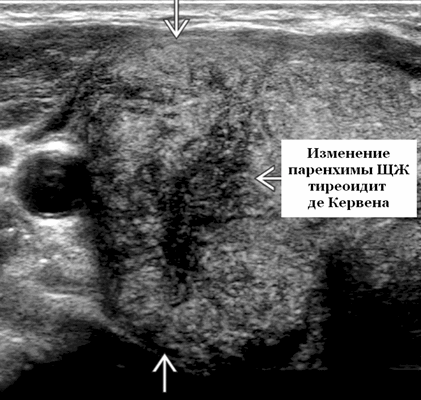

Начинается подострый тиреоидит с общей слабости, ухудшения самочувствия, повышения температуры, появления болей в области щитовидной железы, усиливающихся при ощупывании железы или движениях. В ряде случаев может возникать раздражительность, плаксивость, учащение пульса, похудание - как проявление развивающегося при подостром тиреоидите тиреотоксикоза, связанного с утечкой гормонов из разрушающихся клеток щитовидной железы в кровь. При осмотре эндокринолог обычно отмечает резкую болезненность щитовидной железы при ощупывании, уплотнение ее ткани. Врачи Центра эндокринологии обычно во время приема проводят УЗИ щитовидной железы, которое позволяет выявить характерные участки снижения эхогенности ткани щитовидной железы, не имеющие четких контуров, однако занимающие не весь объем железы. Иногда выявляется один или два очага небольших размеров.

При пальпации (ощупывании) щитовидная железа при подостром тиреоидите резко болезненна, уплотнена. Во время УЗИ щитовидной железы может быть выявлено локальное снижение эхогенности (потемнение) участков щитовидной железы, при этом данные участки имеют неровные и достаточно четкие границы, что весьма специфично для тиреоидита де Кервена.

При проведении ультразвуковой диагностики выявляют плохо выраженный, гипоэхогенный, аваскулярный, субкапсулярный узел щитовидной железы у пациента с болезненным зобом и вирусным продромом. Диффузный зоб с пятнистым, гипоэхогенным, гетерогенным, гиповаскулярным / бессосудистым видом в подострой фазе. Расположение. Очаговый, субкапсулярный в острой фазе. Мультифокальный или диффузный; задействует всю железу, более одной доля в подострой фазе

- Острая фаза. Очаговая, плохо очерченная, гипоэхогенная узелковая область щитовидной железы; субкапсулярный по локации. Нормальная или гипоэхогенная, гетерогенная паренхима щитовидной железы. Болевая реакция при давлении датчиком на пораженную зону. По УЗИ с цветным допплером пораженные участки являются аваскулярными или гиповаскулярными. ± воспалительные узлы в центральном отделе и нижней внутренней яремной цепи